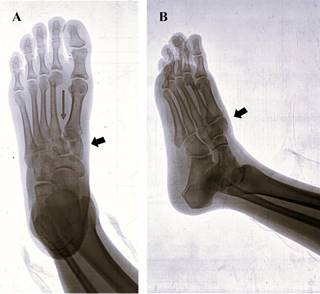

Por un lado, lesiones cuneiformes asociadas a otras fracturas, luxaciones, luxofracturas de una o más cuneiformes adyacentes, han sido previamente descritas.40,41,42 Por otro lado, en trauma complejo de mediopié con lesiones de Lisfranc y compromiso de huesos cuneiformes, en especial la luxación del cuneiforme intermedio, han sido presentadas en forma de reportes aislados de caso (Figura 2 y 3).43,44

Figura 2: Radiografía de pie derecho. A) Proyección anteroposterior; se observa fractura de cuneiforme medial conminuta (flecha corta) y apertura de espacio de Lisfranc (flecha larga). B) Proyección oblicua; se aprecia desplazamiento dorsal de cuneiforme medial (flecha).